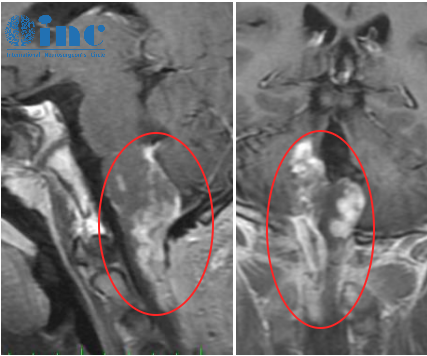

26歲女孩芝芝查出右側丘腦病變,大小約25mm×23mm×24mm,雖然無明顯臨床癥狀,但一家人仍希望盡早解決這個隱患。“風險肯定有,但我知道如何避免。”巴教授在過去40多年中不斷學習和實踐,正是為了掌握如何做到這一點。術前談話時,母親詳盡了解了手術的細節(jié)。這一臺手術,巴教授也將在盡可能切除病灶的同時,保全功能。

右側丘腦病變,大小約25mm×23mm×24mm,雖然無明顯臨床癥狀